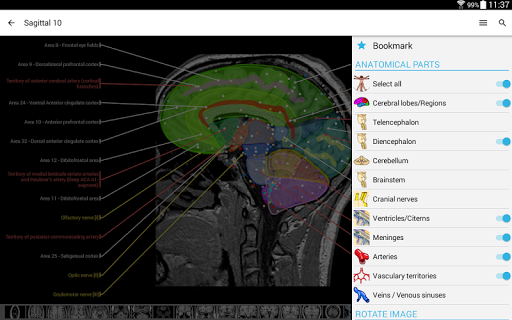

- You can now hide structures one by one (new button inside the description popup) and display them again in the right menu